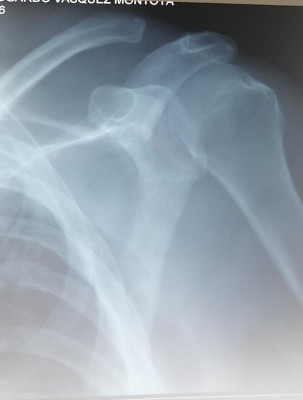

Reducido de luxación acromio clavicular con Dog Bone por arteoscopía de hombro

Envíado por Dr. José Israel Flores Hernández